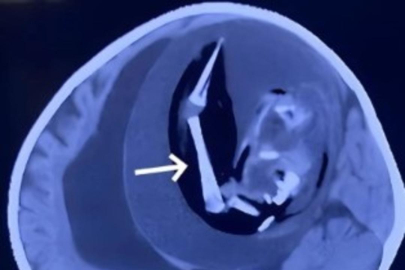

Doktorlar kızın beyninde bilgisayarlı tomografi taraması yaptıklarında, kemiksi bir yapıya sahip büyük bir kitle tespit ettiler. MSNews'e göre doktorlar, ek testler yaptıktan sonra bunun "fetüs içinde fetüs" olarak adlandırılan, normal gelişen bir fetüsün içinde kötü şekilli bir fetüsün yer aldığı nadir bir vaka olduğunu doğruladılar.